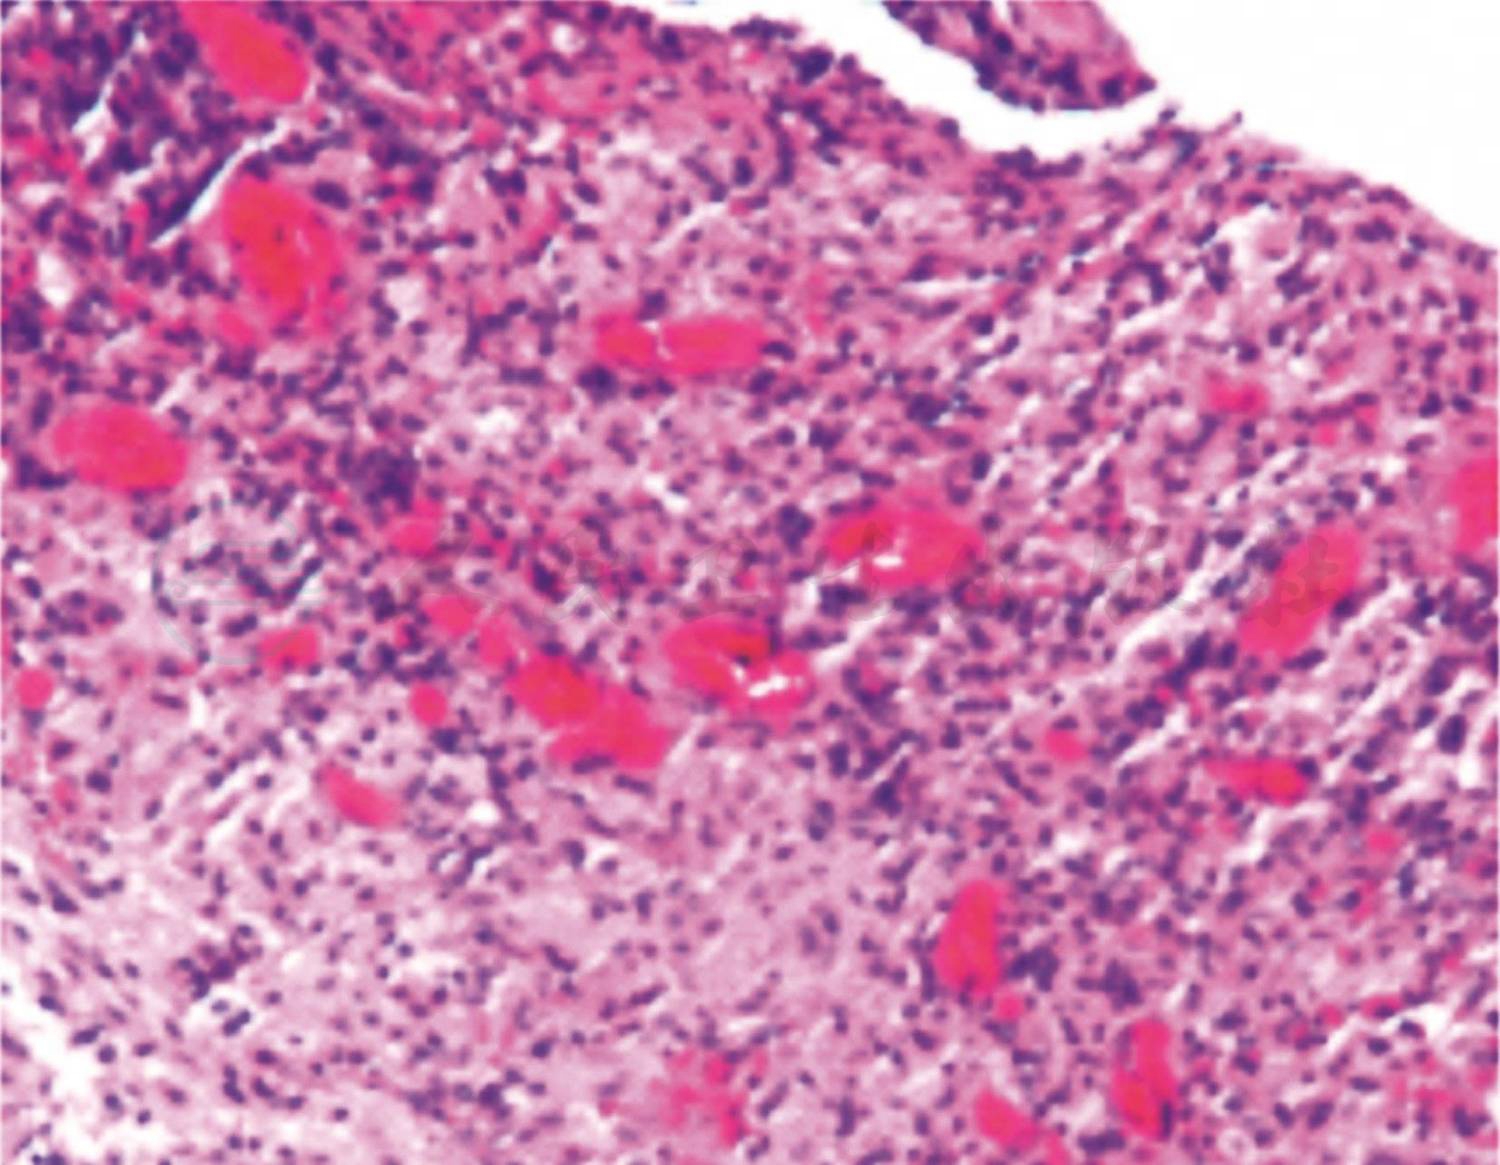

入院第二天行纤维支气管镜检查,镜下可见左肺舌叶(B4、B5)开口处可见一块肿物堵塞大部分管腔(图3),予活检钳钳取部分肿物和留取支气管灌洗液,送病理检查。病理结果回报(图4):(支气管)慢性炎症,局灶见不典型类上皮结节,不除外结核。因此考虑患儿是支气管淋巴结核,结核分枝杆菌突破相邻的支气管内膜,干酪样物进入管腔导致气管腔阻塞。因此增加了抗结核的种类,给予患儿三联抗结核药物(异烟肼、利福平、吡嗪酰胺)口服治疗1个月复查支气管镜。第二次支气管镜下舌叶(B4、B5)开口处可见(图5)黄白色干酪样物质周围被肉芽组织包裹完全堵塞其开口,先用活检钳反复钳取黄白色干酪样物质,并将钳取物分别涂片镜检并送活组织病理检查,考虑常规口服抗结核药物渗透到支气管内膜的浓度小,对局部治疗效果差,因此取了病理后对肉芽组织以及干酪样物进行4次冷冻治疗(每次冷冻时间30~60秒不等)和反复多次钳取,治疗结束后,B5支气管开口得以暴露(图6),其支气管管腔开口通畅,可见正常B5亚段结构,但B4支气管开口仍被肉芽组织覆盖(图7)。分别在第2天后、2周后、1个月后、2.5个月后、6个月后进行5次支气管镜下钳取和冷冻治疗。6个月后第七次支气管镜显示,镜下可见左肺舌叶B5开口通畅,舌叶B4开口形成瘢痕狭窄,2.8mm支气管镜可通过,远端亚段结构正常。复查肺CT可见(图8):左肺上舌叶片状高密度影基本吸收,左肺门肿大淋巴结影较前略减小。

图4 第一次支气管镜黏膜活检病理结果